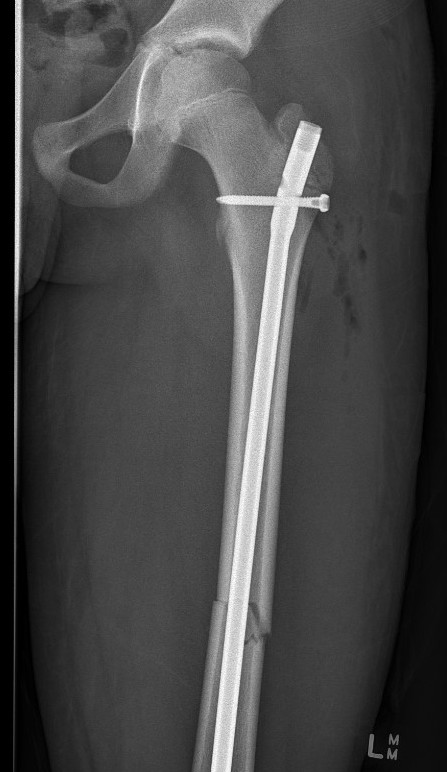

Lateral entry trans-trochanteric adolescent femoral nail

Adolescent Lateral entry Femoral Nail (ALFN)

Keeler et al. J Paediatr Orthop 2009

- 80 femoral fractures treated with lateral entry femoral nails

- no AVN

- no malunion or nonunion

MacNeil et al. J Paediatr Orthop 2011

- systematic review of risk of AVN after used of rigid locking nails

- piriformis fossa AVN rate 2%

- tip greater trochanter AVN rate 1.4%

- lateral entry / trans-trochanter AVN rate 0%

Technique

Synthes lateral entry adolescent femoral nail surgical technique PDF

AO foundation lateral entry adolescent femoral nail (ALFN)

Vumedi lateral entry femoral nail video